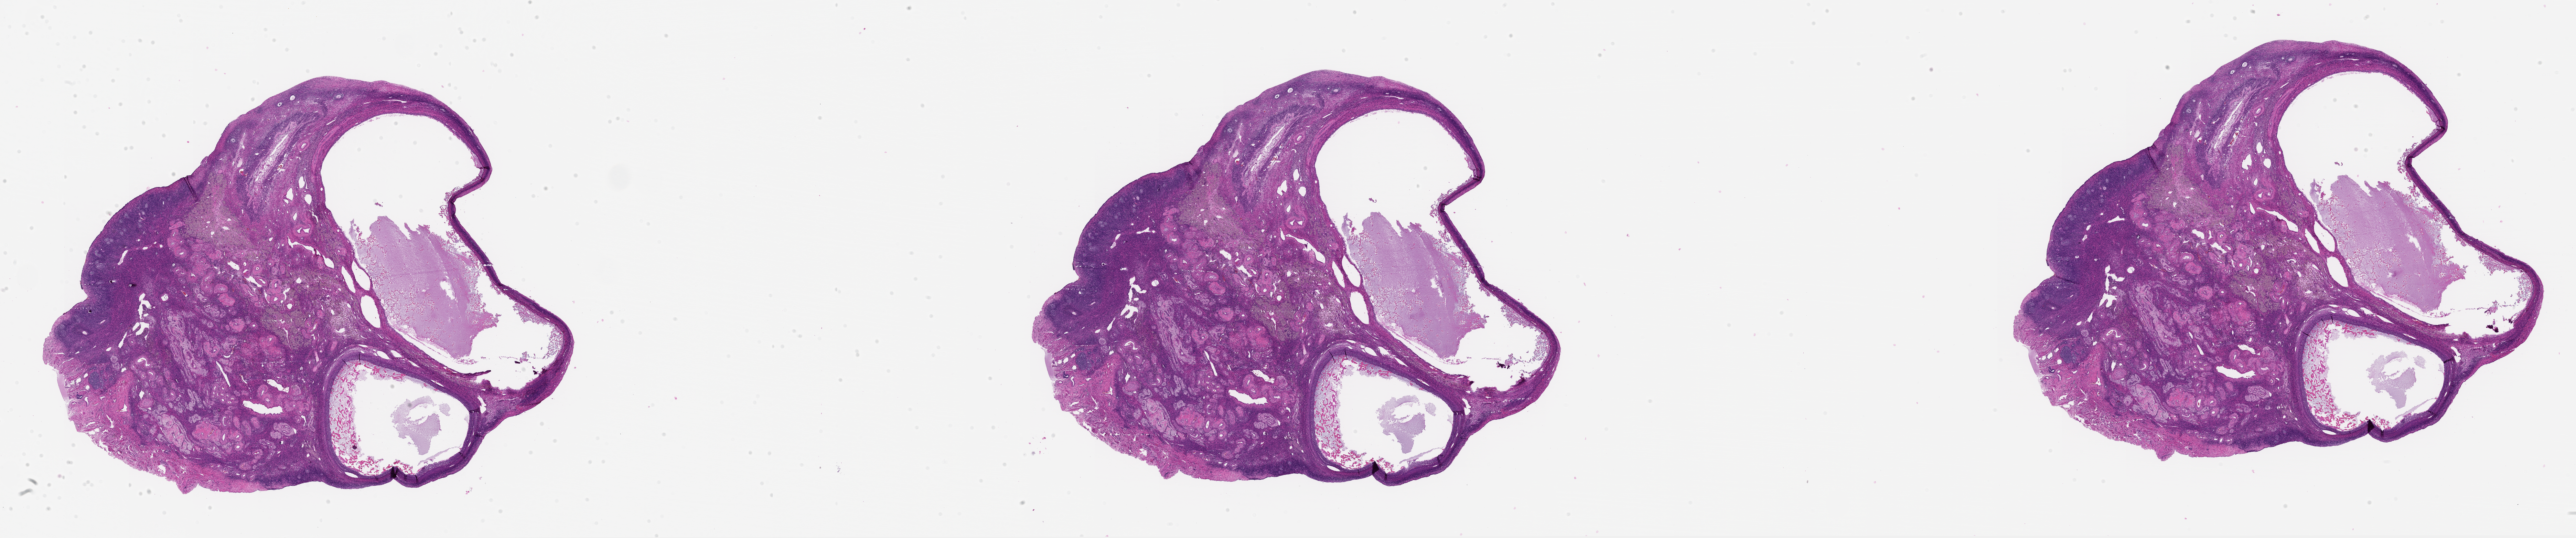

M. Zelinski, 2026, 'Zelinski Lab: Papio hamadryas Donor MZ_PH_39212 Ovary Left Slide 40', https://mother-db.org/MDB0000548, Multispecies Ovary Tissue Histology Electronic Repository, Retrieved: February 16, 2026

Genus: Papio (baboons)

Species: Papio hamadryas (hamadryas baboon)

Donor ID: MZ_PH_39212

Life Stage: aging

Age: 20 years, days

Stage of Cycle: follicular

Accession #: MDB0000548

Ovary position: left

Location: wholeOvary

Section thickness: 5 microns

Fixation: paraformaldehyde4

Stain: hematoxylinAndEosin